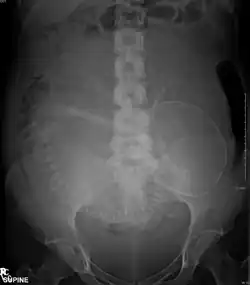

Abdominal radiograph of a pregnant woman

X-rays are a form of ionizing radiation, and are classified as a carcinogen by both the World Health Organization's International Agency for Research on Cancer and the U.S. government.[113][125] Diagnostic X-rays (primarily from CT scans due to the large dose used) increase the risk of developmental problems and cancer in those exposed.[126][127][128] It is estimated that 0.4% of current cancers in the United States are due to computed tomography (CT scans) performed in the past and that this may increase to as high as 1.5–2% with 2007 rates of CT usage.[129]

The risk of radiation is greater to a fetus, so in pregnant patients, the benefits of the investigation (X-ray) should be balanced with the potential hazards to the fetus.[139][140] If there is 1 scan in 9 months, it can be harmful to the fetus.[141] Therefore, women who are pregnant get ultrasounds as their diagnostic imaging because this does not use radiation.[141] If there is too much radiation exposure there could be harmful effects on the fetus or the reproductive organs of the mother.[141] In the US, there are an estimated 62 million CT scans performed annually, including more than 4 million on children.[129] Avoiding unnecessary X-rays (especially CT scans) reduces radiation dose and any associated cancer risk.[142]